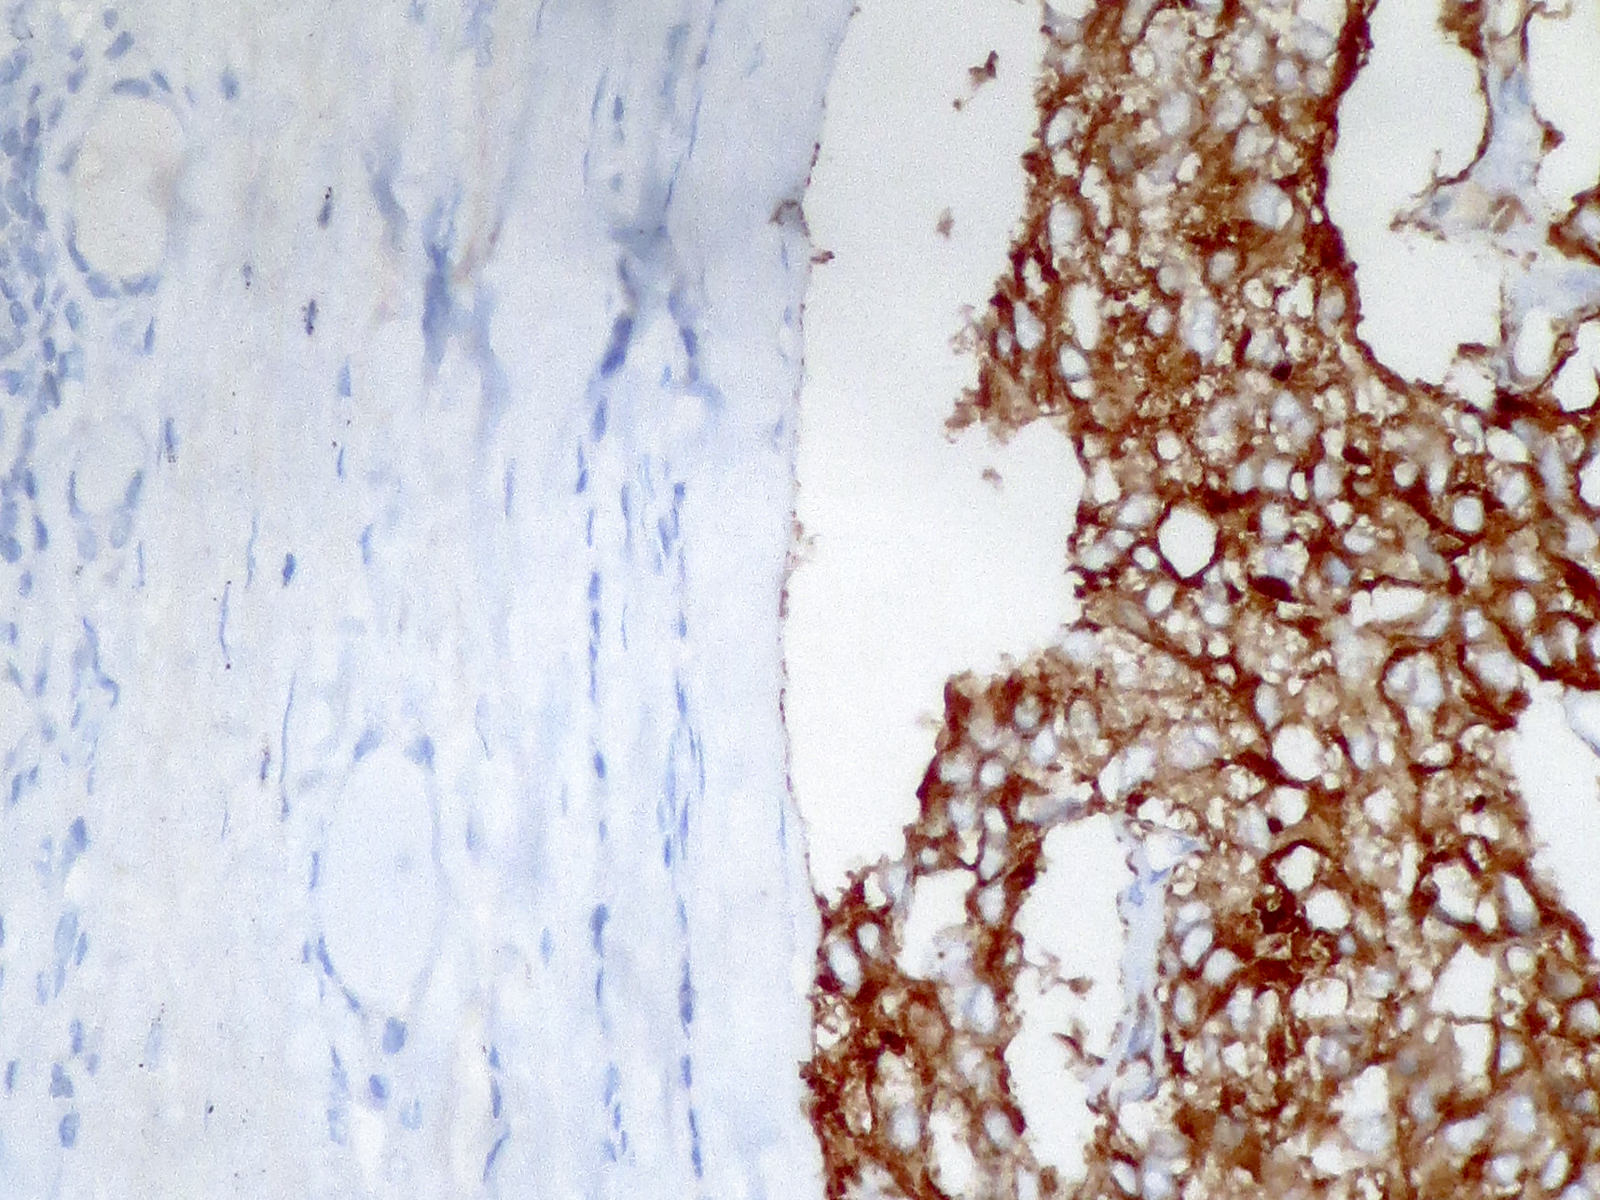

Positive stains

- Calcitonin, CEA, TTF1 (weak to moderate), PAX8 (variable and weak) (Mod Pathol 2008;21:192), Congo red for amyloid

- Calcitonin gene related peptide, ACTH, somatostatin, gastrin releasing peptide, neurotension, low molecular weight keratin, chromogranin A and B, synaptophysin, neuron specific enolase, progesterone receptors (Mod Pathol 1996;9:68)

- Immunocytochemistry for calcitonin, CEA and thyroglobulin is useful with thin layer cytology (Appl Immunohistochem Mol Morphol 2008;16:548)

Negative stains

- Thyroglobulin (entrapped thyroid follicle can be positive), estrogen receptor

Microscopic (histologic) images

Contributed by Shuanzeng Wei, M.D., Ph.D., Joseph Christopher Castillo, M.D. and Mark R. Wick, M.D.